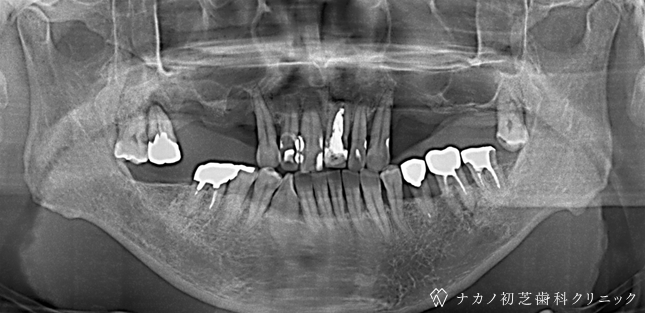

インプラント・7本 (70代男性)

BEFORE

AFTER

年齢 70代男性

治療内容 インプラント治療7本(骨造成の併用)

インプラント治療とは、歯を抜いた所にチタン製の人工歯根を埋入し、その上に歯を入れる方法です。骨を増やすことで、より審美的に治療が出来ました。費用 1本 400,000円(税込 440,000円)

リスク・副作用

腫れ・疼痛・違和感を感じるなどの症状を生じることがあります。